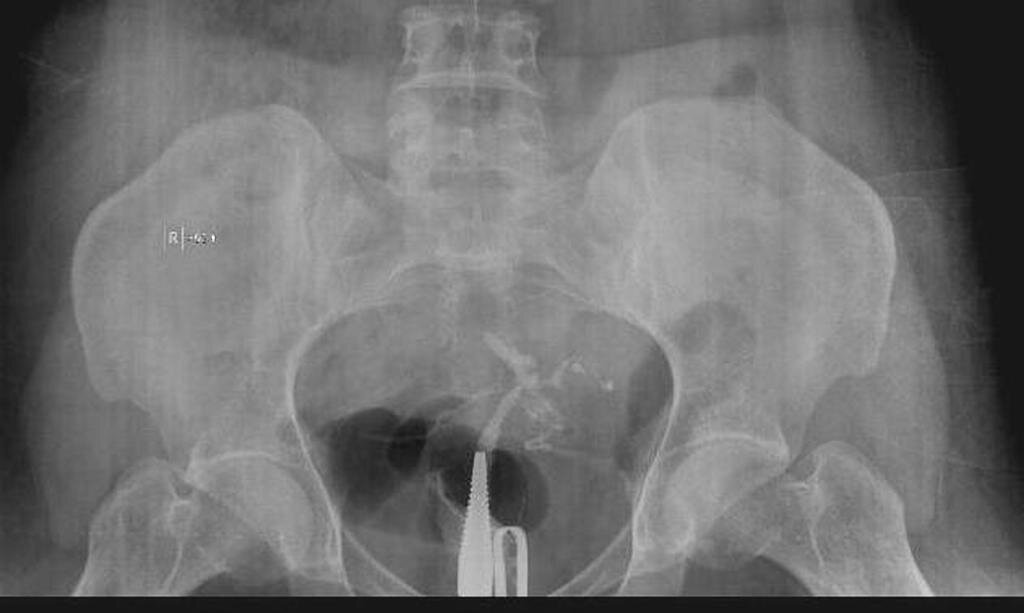

Синдром Ашермана - это редкое заболевание, которое возникает, когда внутри матки или шейки матки образуется рубцовая ткань. Симптомы могут включать сокращение менструаций, боли в области таза и трудности с наступлением или сохранением беременности. В большинстве случаев синдром Ашермана возникает из-за инфекции или осложнения после процедуры расширения и кюретажа, проводимой после неполного выкидыша, во время аборта или после родов, если плацента не отходит должным образом. Выскабливание стенок полости матки (кюретаж) — гинекологическая манипуляция, суть которой заключается в изъятии верхнего слоя слизистой оболочки стенки матки и/или слизистой оболочки шейки матки с помощью специального инструмента — кюретки. Процедура проводится как с лечебной, так и с диагностической целью..

Лаура перенесла такую операцию после рождения дочери в 2016 году. Но когда она заговорила о возможности синдрома Ашермана со своим гинекологом, они отвергли эту идею, отметив, что такое состояние исключительно редко встречается. Однако, Лаура не успокоилась и решила обратиться к другому гинекологу, специалисту по синдрому Ашермана. В следующем месяце она и ее муж Том пришли на прием к профессору Ванкайи, который поставил Лоре диагноз "синдром Ашермана 3 стадии". "Через месяц я вернулась для лечения", - вспоминает она. "А уже через два месяца после этого мне удалось забеременеть".

Лечение синдрома Ашермана включает в себя операцию по удалению рубцовой ткани. Иногда требуется более одной операции в зависимости от степени рубцевания.